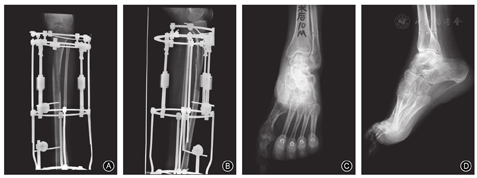

主要指关节挤压、关节炎、关节脱位或半脱位等,往往继发于软组织挛缩未及时纠正,从量变到质变、影响肢体功能,是较严重的并发症。文献报道当肢体延长超过肢体长度的20%时,关节性并发症的数量和严重程度明显增加[10]。如股骨延长时可造成膝关节脱位或半脱位,髋关节内压力增加可诱发髋关节脱位或半脱位[22,23],或股骨头变形,在原有关节结构异常或肌力失衡、关节不稳时更易发生。胫骨延长常可发生踝关节挤压,关节间隙变窄(图3),以致继发性踝骨关节炎等,应提起重视。